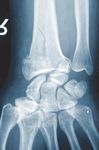

C1 Fraktur, Versorgung mit volarer Platte (breit) und Ulna-Hakenplatte

Präoperativ

Postoperativ

Klinischer Fall und CT-Aufnahmen mit freundlicher Unterstützung der

Klinik und Poliklinik für Unfall-, Hand- und Wiederherstellungschirurgie

Universitätsklinikum Gießen und Marburg GmbH